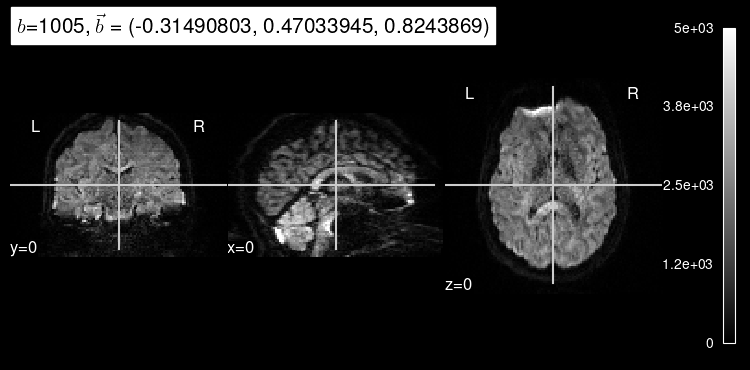

We can also get some insight into how a particular diffusion-weighted orientation looks like by selecting them with the argument index

.

dmri_dataset.plot_mosaic(index=10, vmax=5000);

Diffusion that exhibits directionality in the same direction as the gradient results in a loss of signal. As we can see, diffusion-weighted images consistently drop almost all signal in voxels filled with cerebrospinal fluid because there, water diffusion is free (isotropic) regardless of the direction that is being measured.

We can also see that the images at index=10

and index=100

have different gradient strength (”b-value”).

The higher the magnitude of the gradient, the more diffusion that is allowed to occur, indicated by the overall decrease in signal intensity.

Stronger gradients yield diffusion maps with substantially lower SNR (signal-to-noise ratio), as well as larger distortions derived from the so-called “Eddy-currents”.